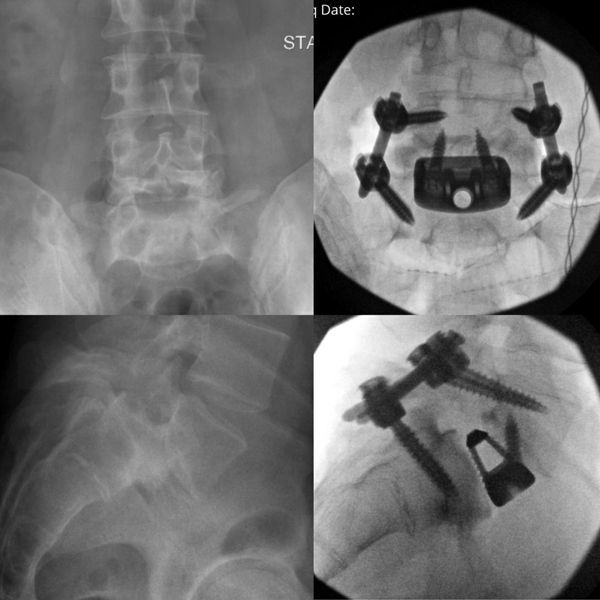

We achieved all of our surgical goals for him today, including anatomic restoration of his lordosis, reduction of his slip, restoration of his foraminal height (decompressing his L5 nerve roots), and stabilization of L5/S1, through an ALIF and a minimally invasive (1.5 inch incision b/l) posterior approach.

“Restoration of anatomic lordosis and alignment at L5/S1 with an ALIF and percutaneous screws, which allowed my patient a faster recovery with less pain.”